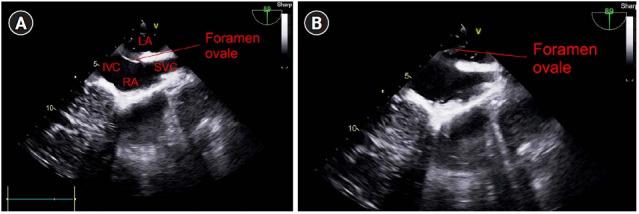

A 70-year-old male with hepatic cell carcinoma underwent laparoscopic hepatectomy. Though his vital signs were stable during the initiation of surgery, they became unstable during the procedure. The surgeon detected portal vein rupture, and transesophageal echocardiography was subsequently performed. A large amount of gas in the heart chamber and paradoxical embolism through a patent foramen ovale due to a right-to-left shunt were observed. We treated the symptoms, and the surgery was completed without any further issues.